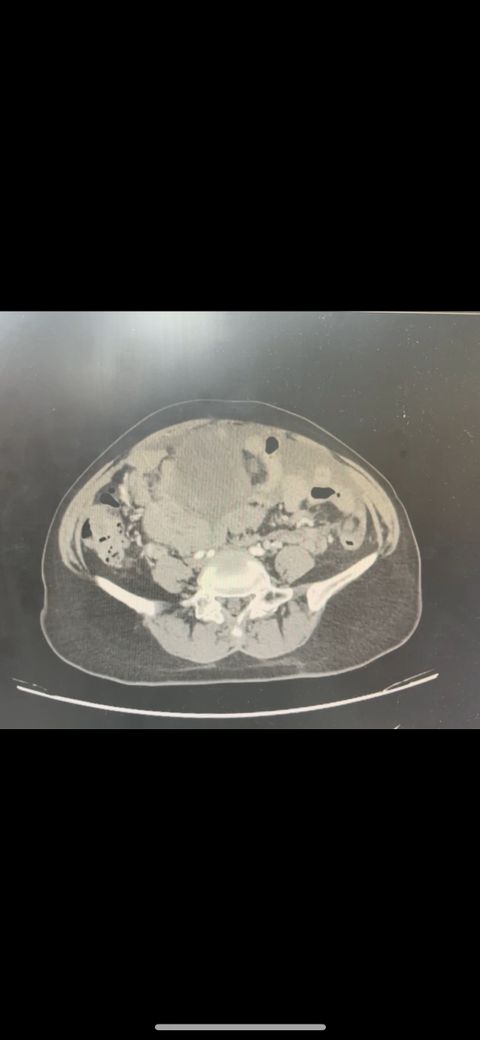

복부 ct (contrast) 영상 판독해주세요!!

어제 복부 ct 촬영하였는데 판독 하려면 시간이 걸려서 미리 알 수 있을까요? 지금 증상은 윗배가 많이 나왔고 허리 아프고 조금만 밥 먹어도 배부른 상태입니다..

• 1번 째 사진

어제 말씀드린대로 자궁 쪽에 불규칙한 음영들이 보이고 있어 물혹이 있는 것으로 의심해 볼 수 있으며, 이외에 복부에 가스가 조금 차있거나 비장이 약간 커져 있는 듯한 모습이 보이나 일부 단면만으로 유추한 것이라 판독 상 틀릴 가능성도 있겠습니다.